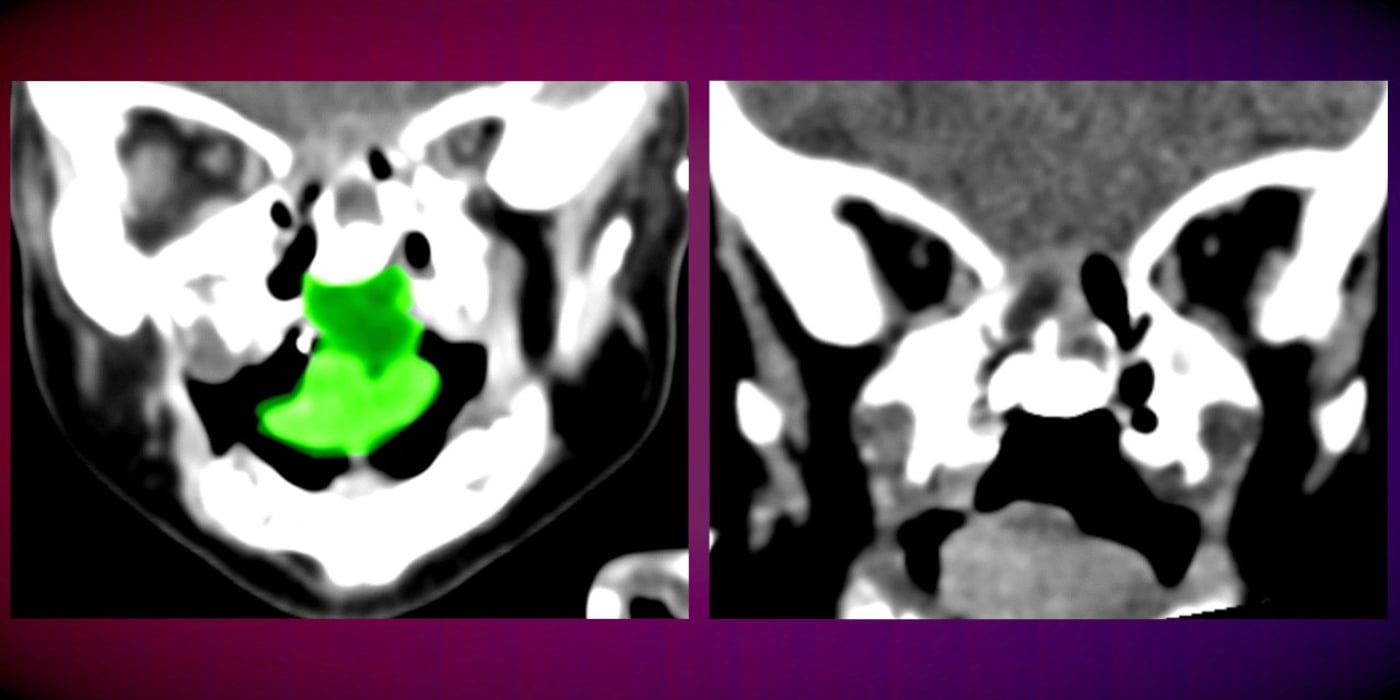

י' נולדה עם מום מסכן חיים – גידול נדיר ומסיבי שהתפתח בחלל הפה והלוע שלה בעודה ברחם אמה ותפס חלק ניכר מהאזור. בשל גדלו של הגידול, התינוקת סבלה מחסימה של נתיב האוויר ואי יכולת להיות מוזנת באופן טבעי, דרך הפה.

במהלך הניתוח, שארך מספר שעות, ביצע צוות רב תחומי כריתה של הגידול החוסם בשלמותו, תוך שמירה על רקמות בריאות שנמצאות מסביבו. ההליך הכירורגי העדין, אותו ביצעו ד"ר עומרי אמודי, וד"ר טל קפושה מהמחלקה לכירורגיה פה ולסתות בניהולו של פרופ' עדי רחמיאל, וכן, ד"ר וסילה ראצ'ה מרדים בכיר, הסתיים בהצלחה ובסופו הועברה התינוקת להמשך התאוששות ביחידה לטיפול נמרץ ילדים, שם שהתה מספר ימים.